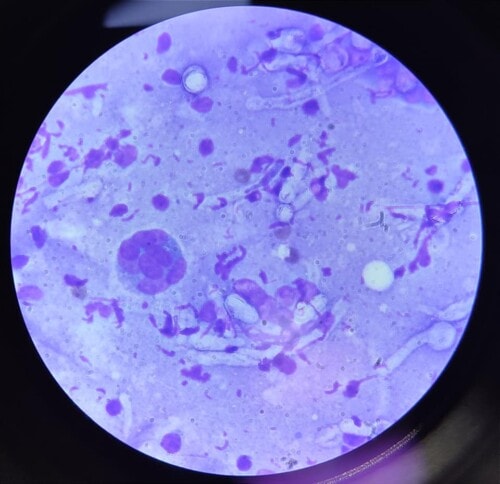

Un traitement antifongique systémique à base de kétoconazole (8mg/kg par jour) associé à un traitement topique d’une solution d’enilconazole diluée au 50ème à raison d’une application tous les 3 jours pendant 6 semaines est mis en place. Après 1 mois de traitement, une nette amélioration clinique sans guérison complète est rapportée (contact téléphonique) puis, la chienne est perdue de vue pendant 4 mois avant d’être de nouveau présentée en consultation pour une récidive. La cytologie montre la présence de polynucléaires neutrophiles majoritairement dégénérés, de macrophages géants multinucléés et de très nombreuses structures fongiques (hyphes, spores… photo 7).

Photo 7 : aspect cytologique des lésions : notez la présence d’hyphes septés et ramifiés non pigmentés et de cellules géantes multinucléées (macrophages).